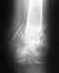

Мальчик занимается спортом - баскетбол с шести лет вместе с братом (двойняшки). До прошлого лета никаких проблем не было. Но после приезда из спортлагеря и простудной болезни стали болеть колени. У брата (если эта информация важна ни тогда, ни сейчас никаких проблем нет, нагрузки на тренировках получали одинаково). После двух месяцев боли правого колена (боль появляется при нагрузках - в основном при резком беге, ускорениях, а также при сгибании и разгибании колена в крайние положения) мы сдали анализ на ревматоидный артрит (анализ отрицательный), снимки колена и показали спортивному врачу. Диагноз был поставлен, что это у мальчика болят шляттеры. На два месяца он прекратил тренировки и упражнениями тренировал (закачивал) правую (и заодно левую ногу). Однако к новому году тенденция поменялась, правое колено стало проходить, а левое наоборот беспокоит, за это время боли так и не ушли. Мальчик начал тренировки (по возможности) в зале. К весне правое колено перестало болеть полностью но стало очень сильно болеть левое. После одного из турниров к боли добавился отек (колено довольно сильно опухло) и болело не позволяя делать активные физические упражнения и нагрузки. Нами были сделаны повторно снимки обеих колен (прикреплены). Все это время (уже 9 месяцев) постоянно мажем коленные суставы вольтареном. Хочется попросить у вас профессиональной помощи и по возможности (если сталкивались с подобными ситуациями) порекомендовать наши действия и какой можно поставить диагноз. Заранее спасибо всем за ответы и советы!